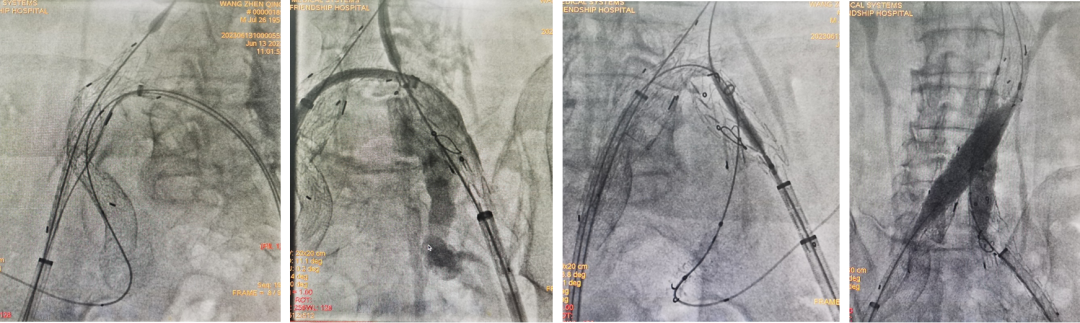

病情:患者男,71岁,双侧髂总动脉并左侧髂内动脉瘤,左侧髂总动脉起始部向右侧严重折曲,担心支架耐弯折性。

策略与操作:双侧差异化重建,右侧髂内动脉主干植入IBE支架;左侧髂内动脉壁支植入G-iliac™支架,通过右股入路配合可调弯导管超选至迂曲段。

右侧IBE,左侧IBD(经右股入路,可调弯导管与12F戈尔长鞘配合进入G-iliac及左侧髂内)

随访结果:术后2年CTA:左侧髂内动脉壁支支架通畅,折曲部位无狭窄或断裂,验证G-iliac™支架的柔顺性与耐久性。